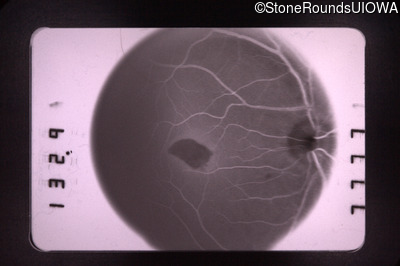

Fluorescein Angiography - Right - 20/70 -1 cc

Exemplar